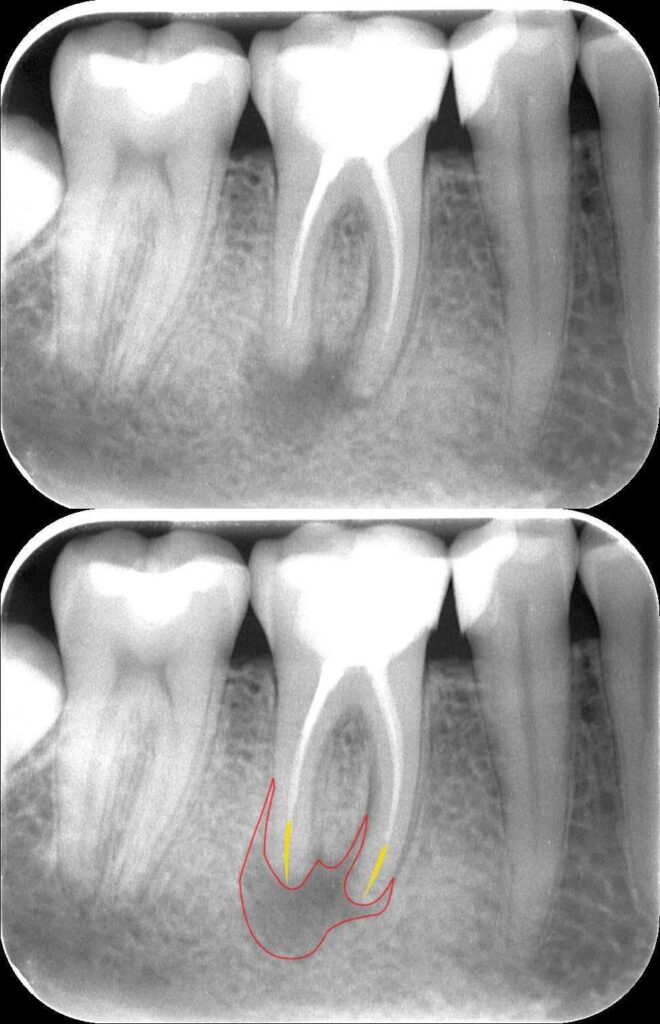

Dr. Kovács Kitti páciense egy három éve készült gyökértöméssel kapcsolatos panaszával kereste fel rendelőnket. A kérdéses fog az utóbbi időben bizonytalan panaszokat produkált. Néha kifejezetten fájt, néha a páciens „érezte”, hogy van foga, néha pedig teljesen panaszmentes volt. A vizsgálatot egy kis röntgenfelvétel készítésével kezdtük, majd ezt tüzetes szájüregi vizsgálat követte. A fog kopogtatásra érzékeny volt, illetve a röntgenfelvételen egyértelműen látható a csontban lévő krónikus gyulladás (amelyet az alsó képen pirossal rajzoltunk körbe), illetve az ezt kiváltó ok, a rövid gyökértömés (amelynek hiányzó szakaszát sárgával jelöltük).

mikroszkópos gyökérkezelés 1.kép